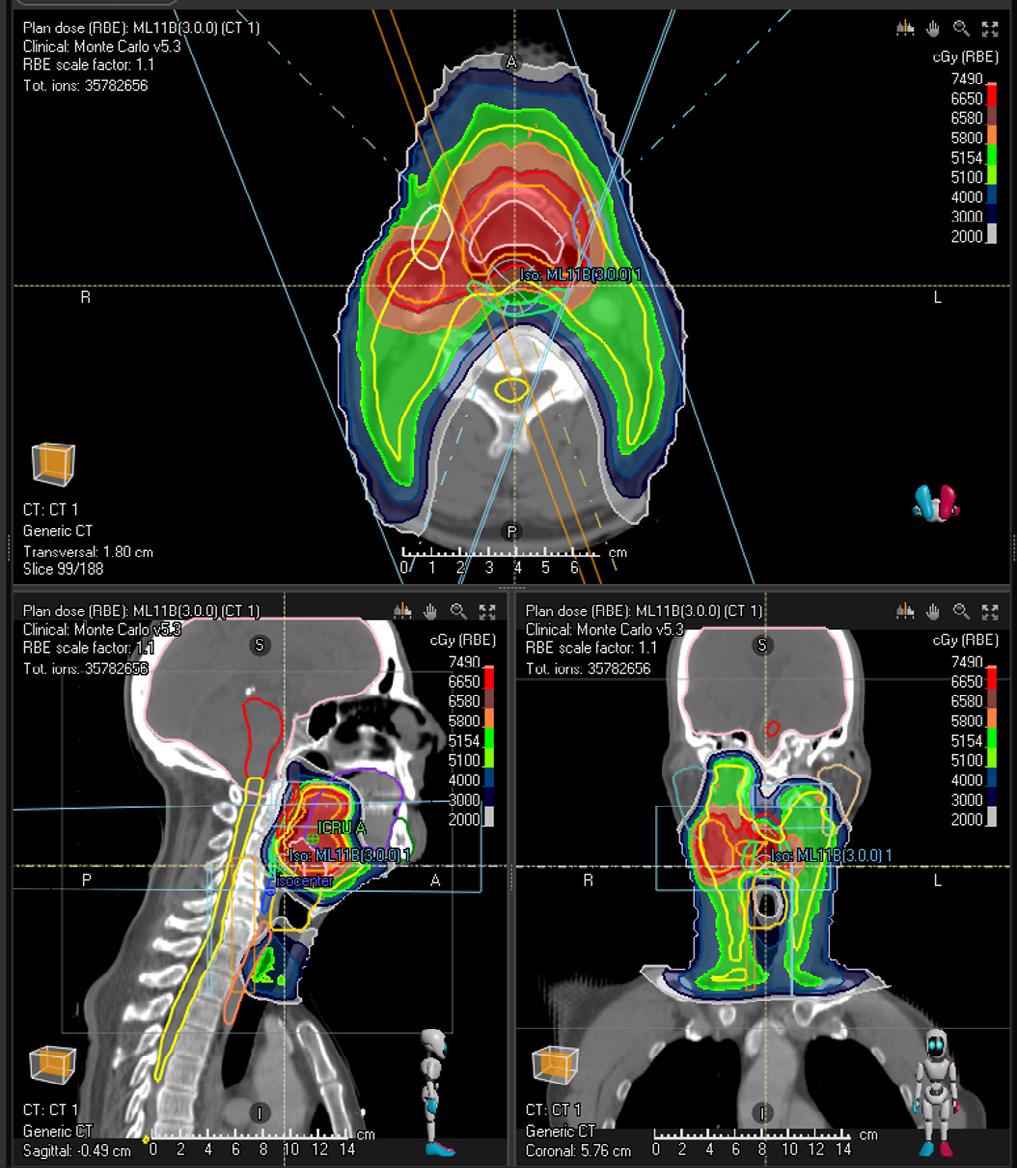

ROI

CTV High

CTV Low

MODEL OVERVIEW

Treatment site Head and neck

Modality Protons

Treatment technique Validated for pencil beam scanning

Primary prescription cGy [RBE] 7000

Number of fractions 35

Dose per fraction cGy [RBE] 200

* Subject to regulatory clearance in some markets. Not for marketing in the USA or Canada.

Clinical goals

At least 6650 cGy dose at 98.0 % volume

At most 7490 cGy dose at 0.0 % volume

At least 5154 cGy dose at 98.0 % volume

At least 5100 cGy dose at 98.0 % volume

CTV High At least 6580 cGy dose at 98.0 % volume

Spinal Cord At most 4500 cGy dose at 0.0 % volume

Brain

Cochlea L/R

Parotid L/R

At most 5800 cGy dose at 1.0 cm³ volume

At most 6800 cGy dose at 0.0 % volume

At most 4500 cGy dose at 50.0 % volume

At most 5500 cGy dose at 5.0 % volume

At most 2600 cGy dose at 50.0 % volume

Constrictor Muscle I/M/S At most 5500 cGy dose at 50.0 % volume

Brainstem

At most 5400 cGy dose at 0.0 % volume

Submandibular Gland L/R At most 3500.0 cGy dose at 50.0 % volume

Cavity Oral At most 3000 cGy dose at 50.0 % volume

Esophagus S At most 3000 cGy dose at 50.0 % volume

Optic Nerve L/R At most 5400 cGy dose at 0.0 % volume

Eye L/R At most 3000 cGy dose at 0.0 % volume

Lacrimal Gland L/R At most 2500 cGy dose at 50.0 % volume

Glottis At most 4000 cGy dose at 50.0 % volume

Larynx SG At most 4000 cGy dose at 50.0 % volume

Bone Mandible At most 7200 cGy dose at 0.0 % volume

Validation patient example